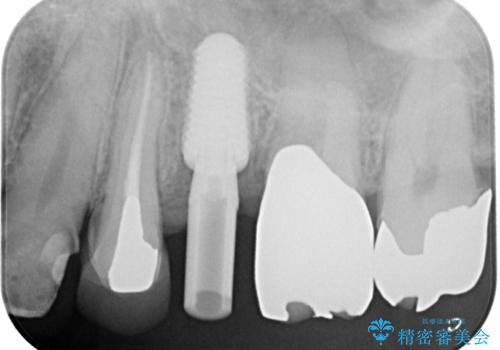

患者様の身体的・時間的負担を最小限に抑えるため、抜歯即時インプラントを選択しました。

この方法では、抜歯と同時にインプラントを埋入するため、

外科処置は1回のみ

治療期間の短縮

早期の機能・審美回復が可能

といったメリットがあります。